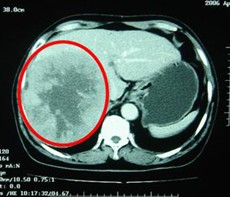

病例1 男,63歲,原發(fā)性肝癌晚期。AFP入院時為13000ng/L, 右肝區(qū)巨大腫瘤約為13×10=130 cm2。治療方案:介入栓塞一個月后肝動脈插管皮下置泵灌注今又生和5-FU。治療后:腹脹,腹痛消失,食欲增加,體重有所增加…聯(lián)系我們